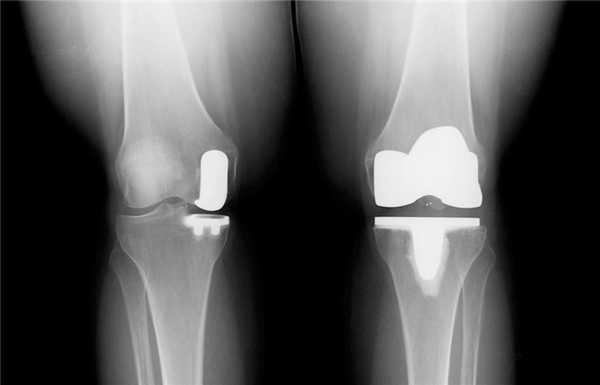

Как это выглядит после операции.

Одномыщелковая замена сустава на рентгене.

Существуют еще такие виды эндопротезов, которые по факту являются одномыщелковыми, но при этом площадь фиксации — как у классического импланта.